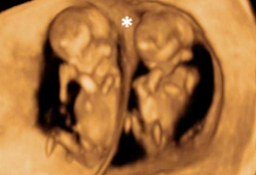

Gemelos de 12 semanas de gestación

La ecografía en 3D de un embarazo gemelar muestra como los dos fetos crecen cada uno en una bolsa amniótica distinta, con su propia placenta. Los embarazos múltiples suelen conllevar más complicaciones que los embarazos únicos. Gemelos de 12 semanas La membrana de separación es claramente...